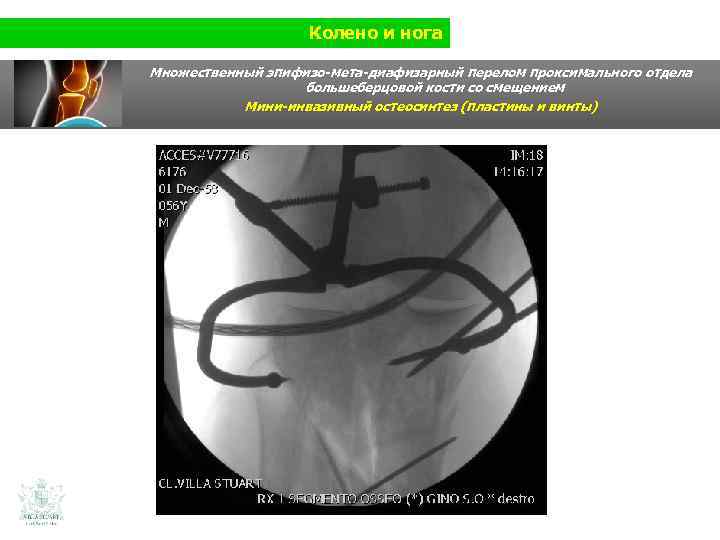

Колено и нога Множественный эпифизо-мета-диафизарный перелом проксимального отдела большеберцовой кости со смещением (Shatzer 6) Мини-инвазивный остеосинтез ( пластины и винты)

Колено и нога Множественный эпифизо-мета-диафизарный перелом проксимального отдела большеберцовой кости со смещением Мини-инвазивный остеосинтез ( пластины и винты)